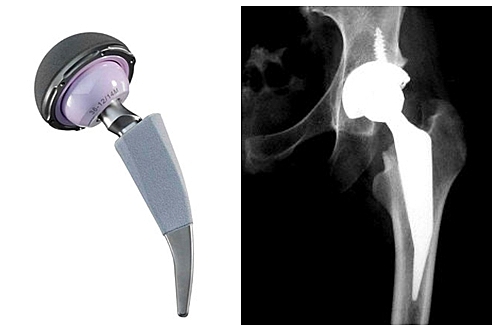

• Actualidad de la artroplastia

Actualidad de la artroplastia

Vástago ha pasado de acero a aleaciones de cromo – cobalto y titanio.

Cabeza femoral se ha pasado de acero a cromo – cobalto y cerámicos.

Se busca eliminar el uso del cemento para la fijación de los componentes protésicos introduciendo nuevas técnicas de fijación como son el bloqueo mecánico y el recubrimiento de los componentes con hidroxiapatita para intentar que el tejido óseo se una químicamente a la hidroxiapatita, y que sea dicha unión la que produzca la fijación del implante.